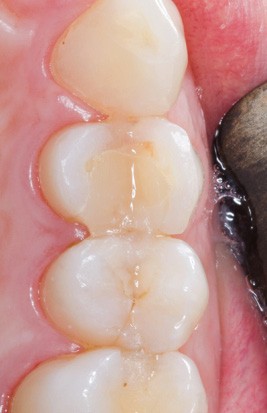

Enfin, un des derniers atouts de l’empreinte optique est la possibilité de réaliser des empreintes des préparations sous digue, ce qui diminue encore les risques d’infiltration des préparations (fig. 5).

Après essayage, le veneerlay est conditionné, puis l’assemblage est réalisé à l’aide d’une colle universelle sous champ opératoire (fig. 15 et 16).